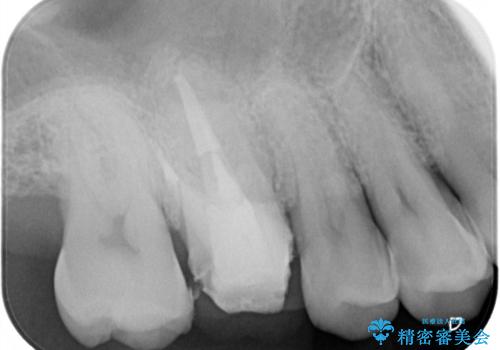

レントゲン上からも、歯の中(根管)が汚れている可能性があることをご説明したところ、根管治療からやり直しをすることになりました。

保険根管治療は回数がかかることが多く、終了予定がわかりにくいです。

当院では、根管治療は長い時間のご予約を頂き、多くの場合2~3回で終わります。

根管治療は歯内の治療なので患者様には見えない場所ですが、ここが細菌で汚染されると激しい痛みや長引く違和感の原因になります。

当院では、清潔な治療を徹底し、顕微鏡を使用した精密な治療を行っています。